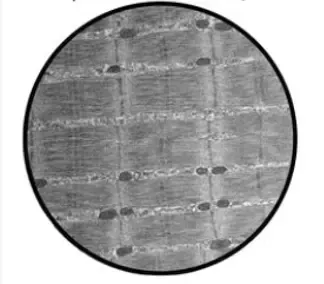

Title: Enhancing muscle strength in aging by targeting the gerozyme 15-PGDH

Multiomic profiling reveals that prostaglandin E2 reverses aged muscle stem cell dysfunction, leading to increased regeneration and strength.

Regeneration of neuromuscular synapses after acute and chronic denervation by inhibiting the gerozyme 15-prostaglandin dehydrogenase.

Primary cilia on muscle stem cells are critical to maintain regenerative capacity and are lost during aging.